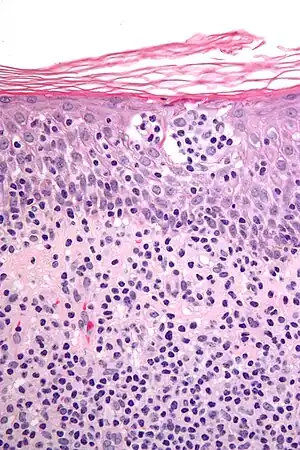

| Micrograph showing cutaneous T-cell lymphoma. H&E stain | |